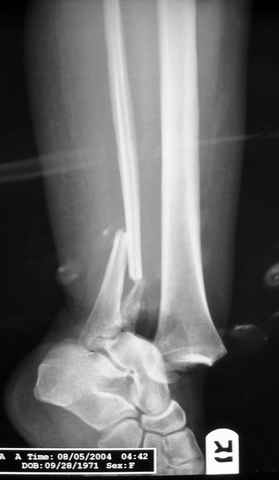

Re: ANKLE FRACTURE

Второй случай сделан из одного разреза